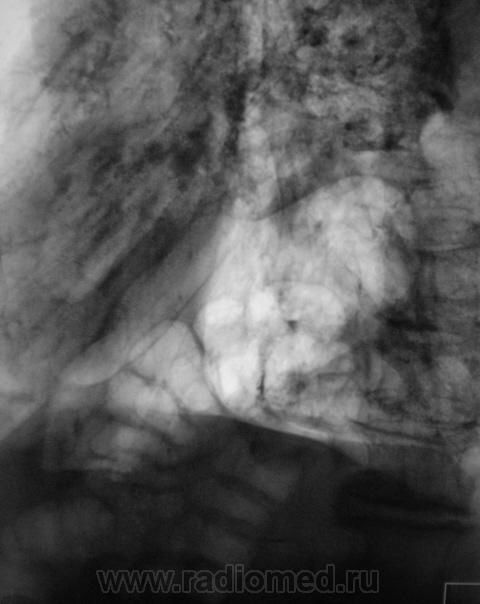

• https://radiomed.ru/sites/default/files/styles/case_slider_image/public/user/12/101.Dela_.JPG?itok=gavyXzg8

Томограммы.

Какие мнения?